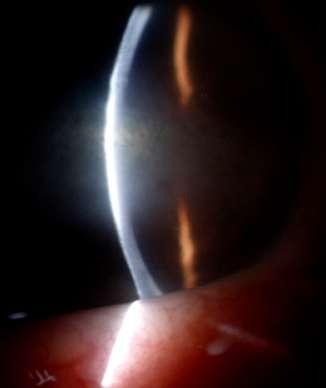

3.B. MELANOMA AMELANÓTICO

Caso aportado por Dr. Osvaldo Weisse

ü Imagen C: Lesión sólida ligeramente irregular, homogénea, de reflectividad media baja con elementos de vascularidad en su interfase. Altamente consistente con melanoma de coroides

ü Mujer 57 años consultó en policlínico por cuadro de disminución de la agudeza visual de hemicampo superior del ojo derecho, indoloro de 1 mes de evolución

ü Imagen B: Subyacente al DR hay una lesion sólida dependiente de la coroides, irregular en base (18.8mm) y altura (1.63)

C

ü Imagen D y E: Lesión coroidea que levanta la macula, asociada a líquido subretinal